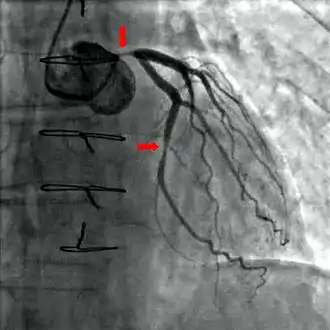

![]() Cateterismo de coronárias mostrando oclusões no ramo principal da artéria coronária esquerda (seta superior) e na ramificação circunflexa da artéria coronária esquerda [en] (seta inferior). |